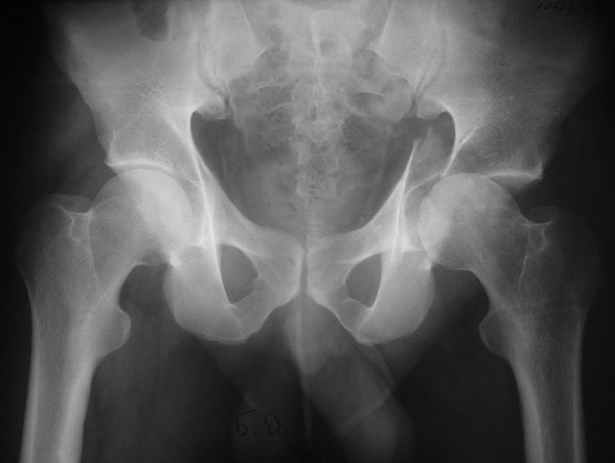

Диагноз- перелом с вовлечением таза, разрыв правого сакро-илиак сочленения vertical shear injury, перелом крыла подвздошной кости?, перелом ацетабулум Т type или Both column?, перелом шейки бедра, перелом проксимального отдела бедра.

перелом крыла правой подвздошной кости, перелом обеих колонн вертлужной впадины, двусторонний перелом лонных костей (С2.2) повреждение передних связок правого крестцово-подвздошного сочленения,

ипсилатеральный перелом шейки и диафиза бедра.